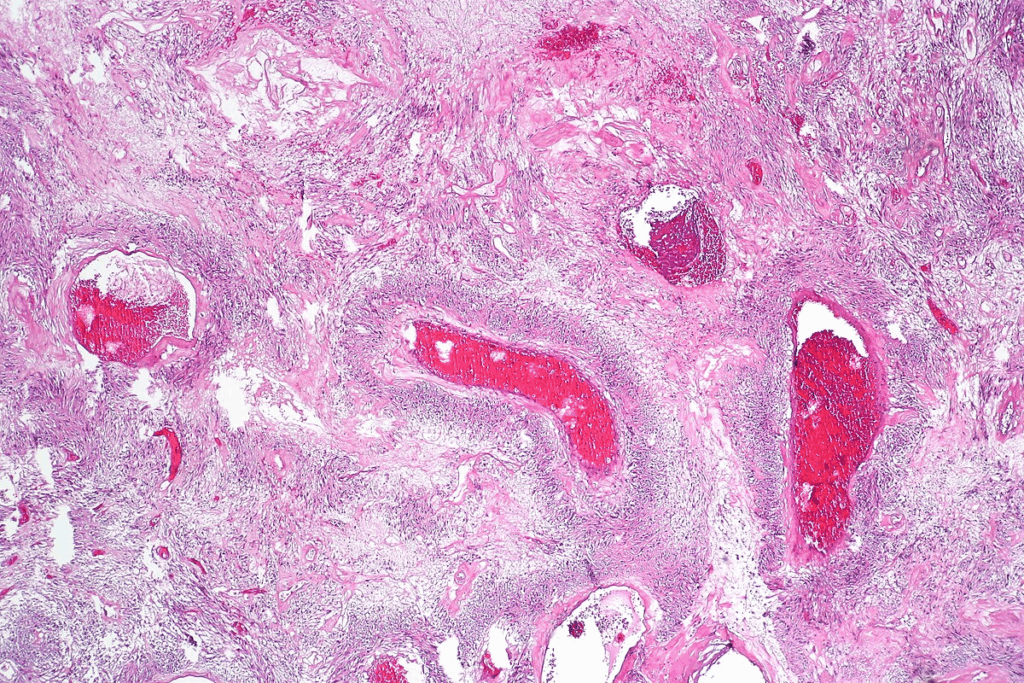

Physical and Histological Properties

Wilms tumor has physical and histological properties that help doctors diagnose it. It usually looks like a big, single mass in the kidney. It has clear edges from the normal kidney tissue.

Looking at the tumor under a microscope shows its three parts: blastemal, epithelial, and stromal. This mix makes it hard to diagnose at times. But, finding anaplasia, with its big, dark nuclei, is a big clue for doctors.